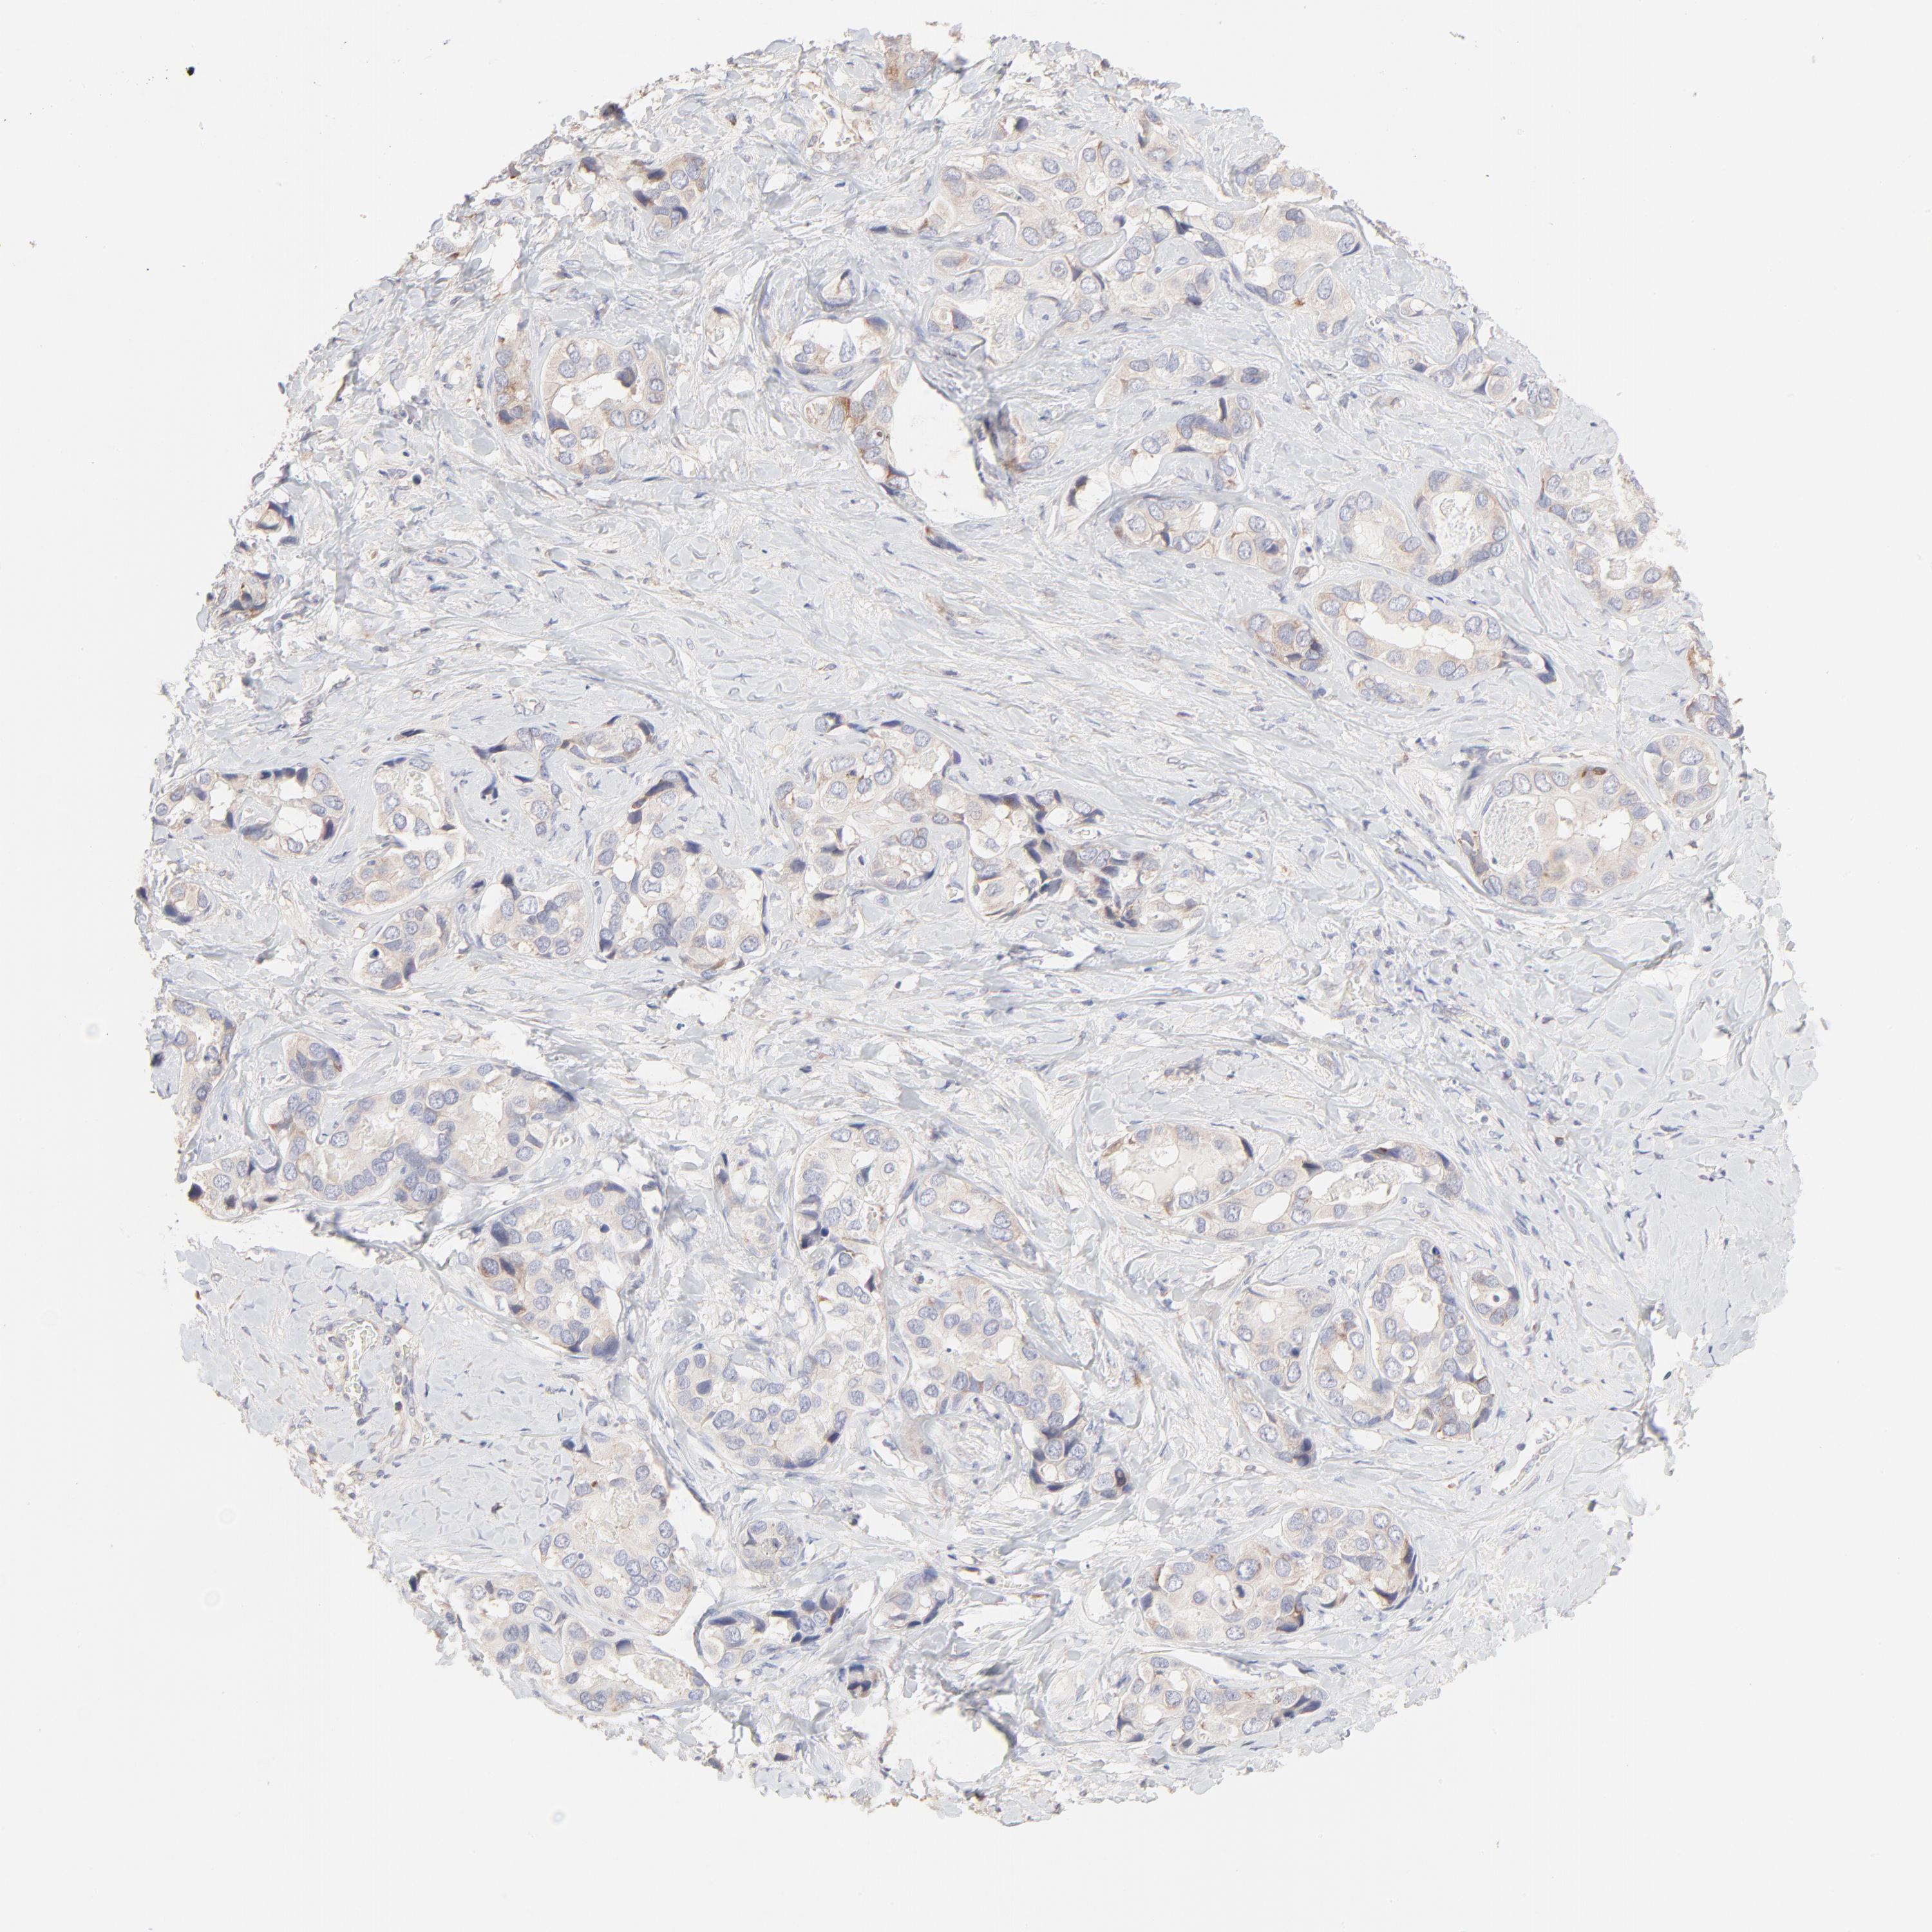

LIVER CANCER - Protein expressioni

A mouse-over function shows sample information and annotation data. Click on an image to view it in a full screen mode. Samples can be filtered based on level of antibody staining by selecting one or several of the following categories: high, medium, low and not detected. The assay and annotation is described here.

Note that samples used for immunohistochemistry by the Human Protein Atlas do not correspond to samples in the TCGA dataset.

Antibody stainingi

Antibody staining in the annotated cell types in the current human tissue is reported as not detected, low, medium, or high, based on conventional immunohistochemistry profiling in selected tissues. This score is based on the combination of the staining intensity and fraction of stained cells.

Each image is clickable and will lead to virtual microscopy that enables deeper exploration of all samples and also displays staining intensity scores, fraction scores and subcellular localization as well as patient and tissue information for each sample.

Antibody HPA003371

Staining

High

Medium

Low

Not detected

Intensity

Strong

Moderate

Weak

Negative

Quantity

>75%

75%-25%

<25%

None

Location

Nuclear

Cytoplasmic/membranous

Cytoplasmic/membranous,nuclear

Carcinoma, Hepatocellular, NOS

Cholangiocarcinoma